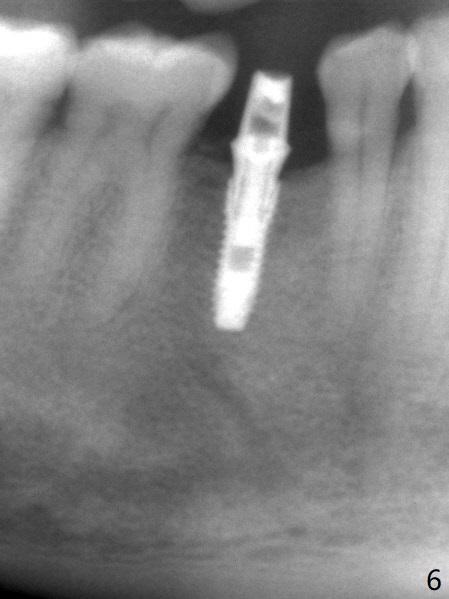

The base of the edentulous ridge at #29 looks wide (Fig.1), but the most coronal portion is the thin soft tissue (Fig.2). It appears that there has been bone resorption since extraction. The initial osteotomy depth is 11.5 mm (Fig.3). Since the Mental Loop seems to be nearby, the depth of subsequent osteotomy (3 mm) remains the same (Fig.4). Although the final depth of osteotomy is 13 mm, the implant placed is short (3.8x11.5 mm, Fig.5,6), as compared to the immediate implant (3.8x18 mm) at the contralateral side (#20). There is mild bone resorption mesially 4 months postop (Fig.7). The crown is loose (poor osteotomy position, guide necessity) 7 months post cementation immediately prior to 18 cementation, although there is no gross bone losss 1 year 7 months post cementation (Fig.8).